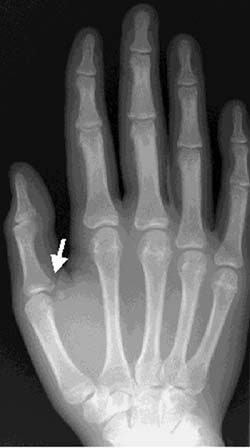

| Anteroposterior view of the right hand reveals an oblique fracture of the proximal and medial portion of the proximal first phalanx (white arrow). The fracture extends into the joint and is in the region of the ulnar collateral ligament. |

This type of an avulsion fracture (skier’s fracture) is often accompanied by complete ligamentous disruption (more than 30° stressed radial deviation and more than 20° difference compared with the uninjured side). Arthrography of the first MCPJ has also been done in the evaluation of UCL disruptions. If the ligament is disrupted, extravasation occurs along the medial side of the joint. If the adductor aponeurosis is interposed between the UCL and the ligament attachment site, it can often be seen as a filling defect.